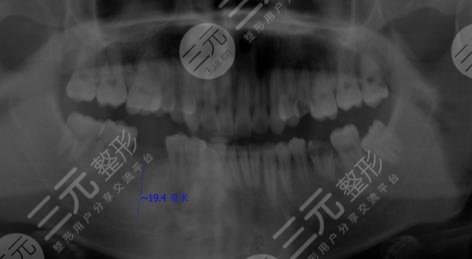

醫(yī)生看了我的牙齒情況之后,為我判斷了幾顆比較需要進行種植牙的地方進行了拔除。大概在拔完牙,一星期后我進行了種植牙,剛種上的時候還是覺得挺不舒服的,但是隨著時間的推移,我逐漸適應了自己的種植牙,并且種植的牙齒比之前更加潔白,它不單單解決了我的口腔問題,還讓我整個人的氣質都上升了不少呢。